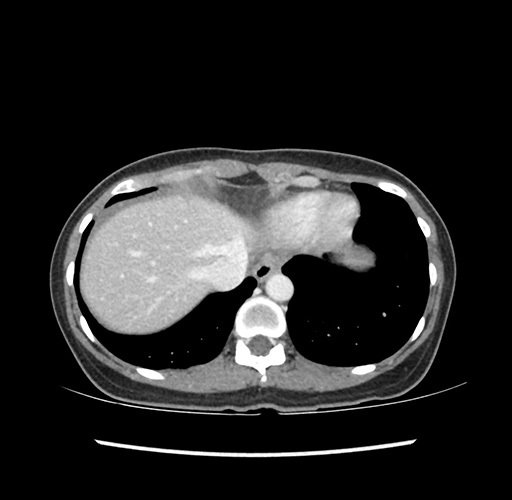

Imaging Analysis

Look through the patient's CT scan to identify any areas of concern for the necessary procedure.

Based on your CT findings, which issue(s) would give reason for "planned slowing down moment(s)" in this case?

Considering a standard left lateral sectionectomy procedure, what step(s) of the operation would you do differently in this case ?